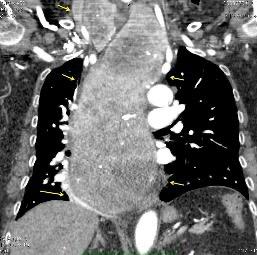

Ganglios retroperitoneales (flechas negras)

germinales del testículo izquierdo Nódulos pulmonares múltiples. (flechas verdes). Ganglios paratraqueales. (flechas amarillas). Dudoso ensanchamiento retrocrural (flechas negras)

Panda A et al. “Straddling Across Boundaries”. Thoracoabdominal Lesions: Spectrum and Pattern Approach. Curr Probl Diagn Radiol, 2015